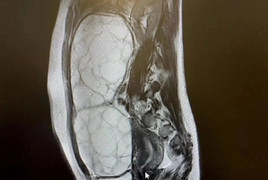

Ngày 22/6 vừa qua, thấy mình không mang thai nhưng ngực thường xuyên tiết ra sữa non và hay bị rối loạn kinh nguyệt, chị T.L đã tìm đến Phòng khám phụ sản thăm khám và được chẩn đoán có một khối u.